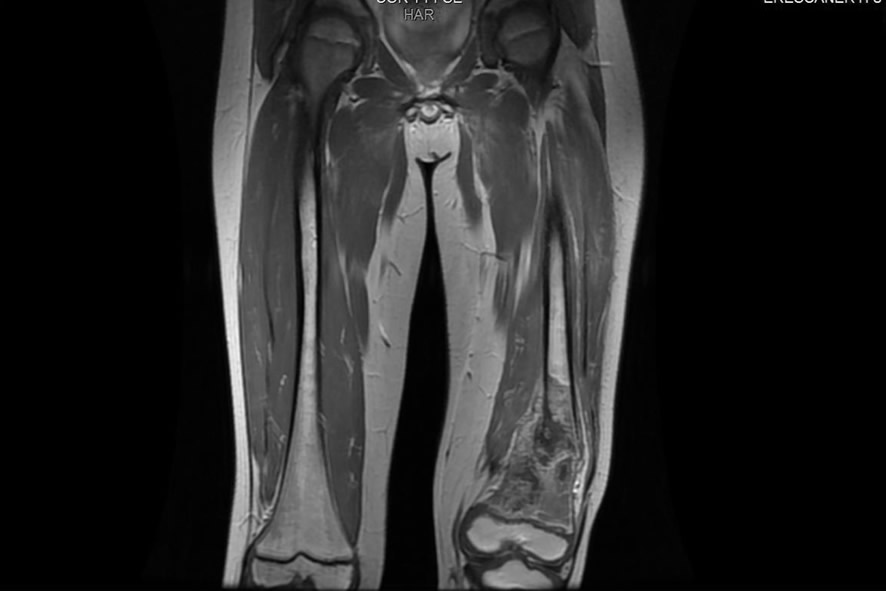

Diagnóstico: Osteosarcoma fémur distal con infiltración de arteria poplítea y nervio ciático

Paciente de 10 años que acude por osteosarcoma de fémur distal extracompartimental que afecta a vasos poplíteos y nervio ciático. La única opción de tratamiento que habían ofrecido era la amputación proximal trans femoral.

Transferencia microquirúrgica de tibia, tobillo y pie, girado 180º, para reconstruir un muñón similar a una amputación BK (debajo de rodilla), usando el tobillo como rodilla.

El resultado funcional fue la curación del tumor (junto a quimioterapia adecuada), mejorando el nivel de amputación. El paciente puede caminar con una prótesis sencilla porque el tobillo funciona como una rodilla.